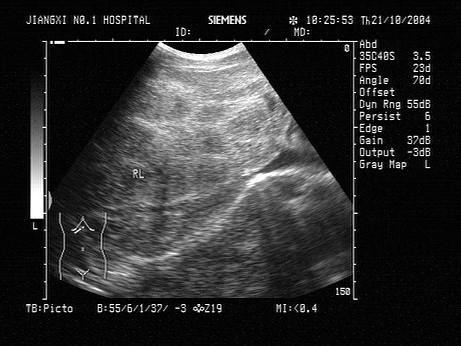

根据肝脏声像图表现,最可能的诊断是?(?)A.原发性肝癌B.血吸虫肝C.结节性肝硬化D.肝炎E.不均匀性脂肪肝

问题 根据肝脏声像图表现,最可能的诊断是?(?)

选项 A.原发性肝癌 B.血吸虫肝 C.结节性肝硬化 D.肝炎 E.不均匀性脂肪肝

答案 B